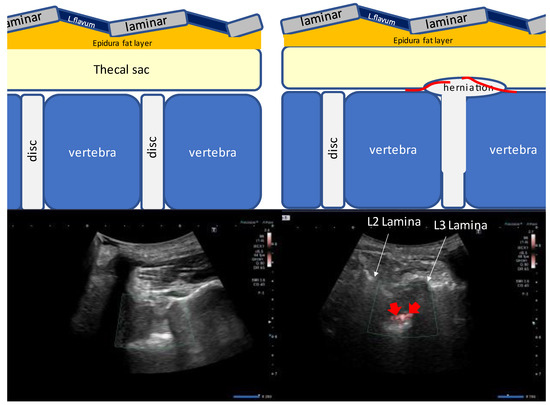

4.1. Measurement of Epidural Space Depth and the Proper Needle Angle (Needle Guide)

4.2. US-Guided Techniques